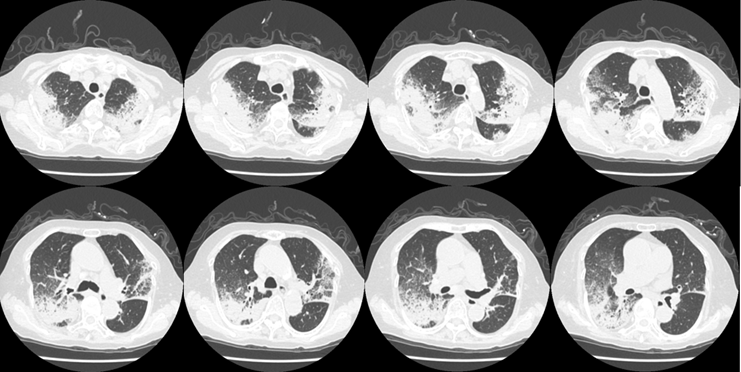

图1~2为COP患者,图1表现为双肺实变,图2为大片实变,患者快速进展为呼吸衰竭。

图1  COP患者胸部CT

图2  COP患者胸部CT进展